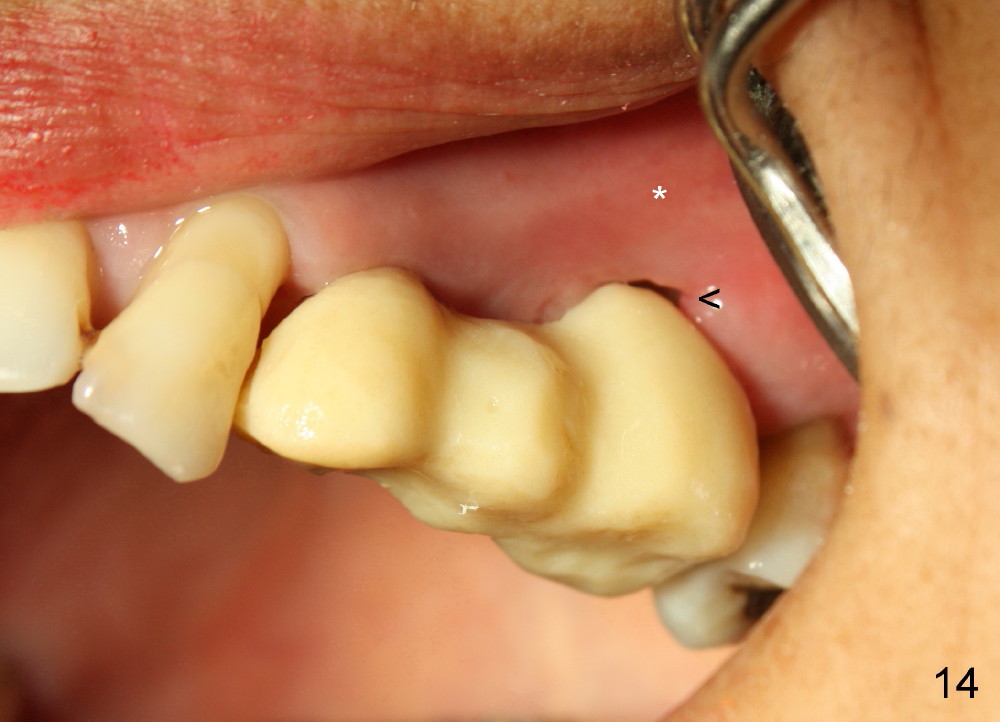

Buccal to #14 implant/abutment is a large defect, which is filled with allograft and Osteogen and covered by collagen membrane (Fig.9 M). The defect at the site of #12 is mesiopalatal, which is repaired in the same fashion (Fig.10: M). The collagen membrane is in turn protected by the "overhang" (extension) of the immediate provisional bridge (Fig.11,12 *). Once the wounds heal (Fig.13, 9 days postop), the extension is trimmed (Fig.14).